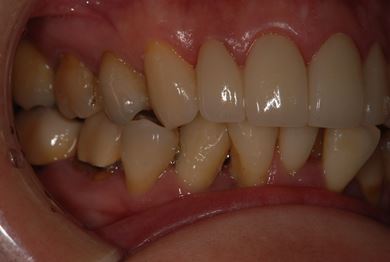

| 性別/年齢 | 女性 / 40歳 | ||||||||||||||||||||||||||||||||

| 主訴 | 前歯のつけ根の黒い部分を見えないようにしたい。 | ||||||||||||||||||||||||||||||||

| 治療方針 | 上顎前歯をセラミック治療にて審美的回復を行う。 | ||||||||||||||||||||||||||||||||

| 治療内容 | オールセラミッククラウン4本(セラミック用土台4本) | ||||||||||||||||||||||||||||||||

| 総治療費 | 573,300円 | ||||||||||||||||||||||||||||||||

| 治療期間 | 3ヶ月 |